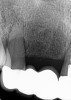

A 63-year-old woman presented with severe pain on biting of tooth No. 19 (Figure 1). Clinically there was pain on percussion and significant periodontal probing along the mesial root. The patient was anesthetized with infiltration anesthesia and the crown was horizontally sectioned from the lingual of the tooth. The remaining tooth was sectioned so the roots could be extracted individually. The socket was fully debrided and an implant was placed (Figure 2), which was prosthetically correct and stabilized in excess of 45 Ncm. The bone was milled to allow for unimpeded placement of a temporization abutment. The initial crown was revised to be the temporary crown in infraocclusion. Cement was extruded extraorally (Figure 3) prior to seating of the temporary restoration. The socket was sealed with the temporary crown and there were no sutures or bone graft (Figure 4 and Figure 5).

The patient was instructed in postoperative care specific to an immediately provisionally restored implant and an antibiotic and analgesic was prescribed. At 4 months, integration was confirmed. The patient was impressed for a final restoration that was cemented within 2 weeks. The final radiograph (Figure 6) and clinical photo (Figure 7) presents a 1-year postoperative demonstrating good esthetics, full bone regeneration, and a steady state of bone to the implant under loading.